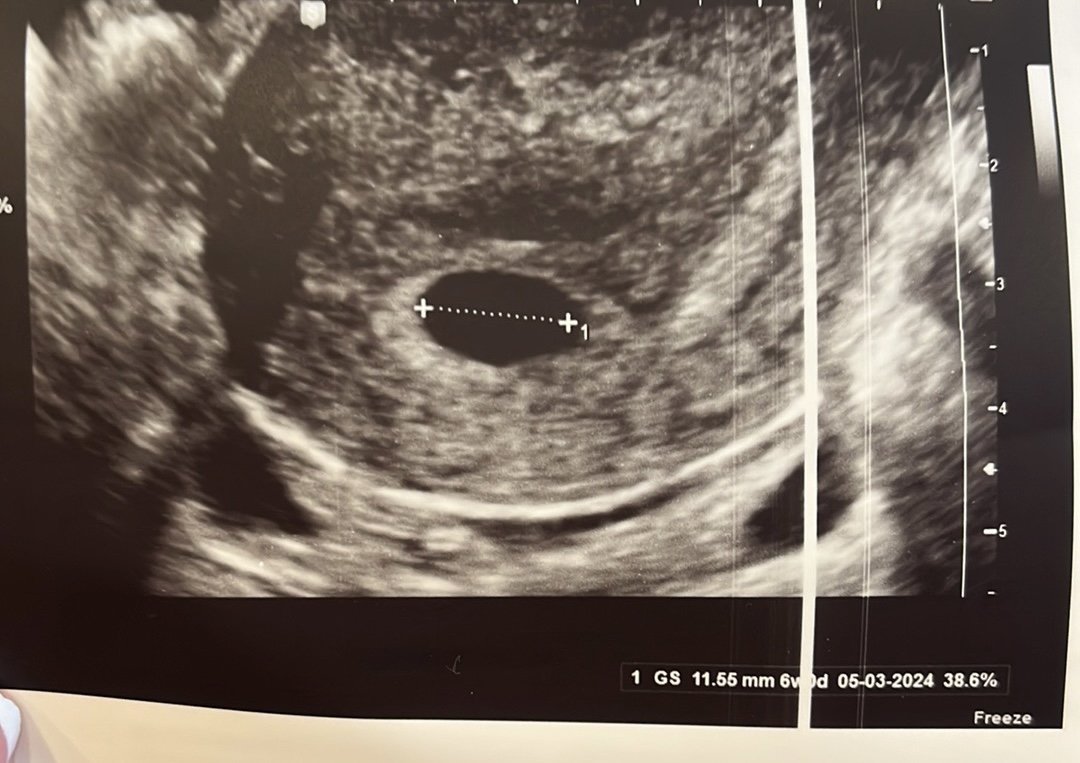

Вчера бях на първи преглед, при АГ с много хубава апаратура. Каза, че има нещо, но все още не може да установи бременност и да ида отново след 2 седмици.

Това ми е втора бременност. С първата, в 6+5 г.с. Се виждаше идеалното мехурче в плодния сак, дори чухме пулс, а този път сакчето ми изглежда празно, отделно всички симптоми, които имах изчезнаха.

Според АГ, сега отговаря на размера си и е в 6г.с, макар че според календара ми съм в 7-ма.